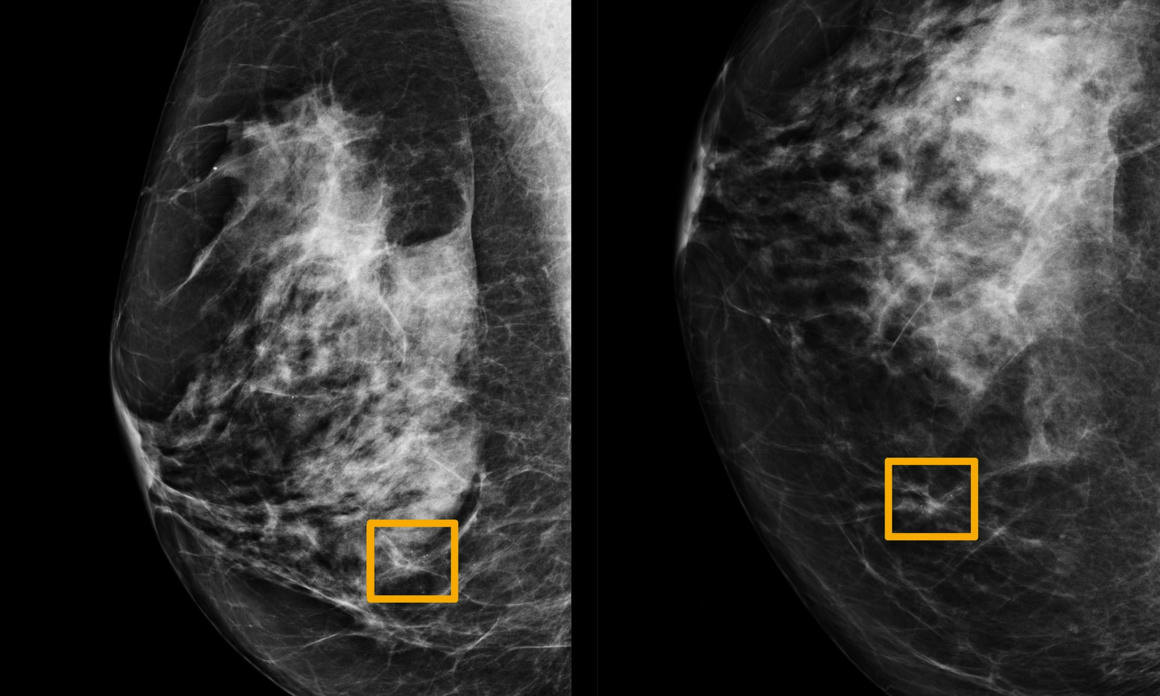

AZ algoritmus jól szerepelt az első teszteken, amikor is első körben kilencvenegyezer nő röntgenfelvételét kellett elemeznie, és öntanulással tökélyre fejleszteni a mammográfiai leletek olvasását. Második alkalommal huszonhétezer felvételen keresztül próbálták a program hatékonyságát (el kellett döntenie, hogy, a kapott elváltozás rákot jelez-e avagy sem). Végül további ötszáz felvételt kapott, melyek tanulmányozására az MI mellett már hat radiológus professzort is felkértek.

Az algoritmus összességében nagyobb pontossággal azonosította a rákot, mivel olyan jeleket is észlelt a képeken, amik a radiológusoknak nem tűntek fel. Valamint figyelmen kívül hagyott olyan területeket, amiket az orvosok tévesen tumornak feltételeztek. Az algoritmus működési elve szerint három különböző módon elemzi a mammográfiai felvételeket, összesíti a kapott eredményeket, majd a kapott kockázati értékeket továbbítja a szakembereknek.